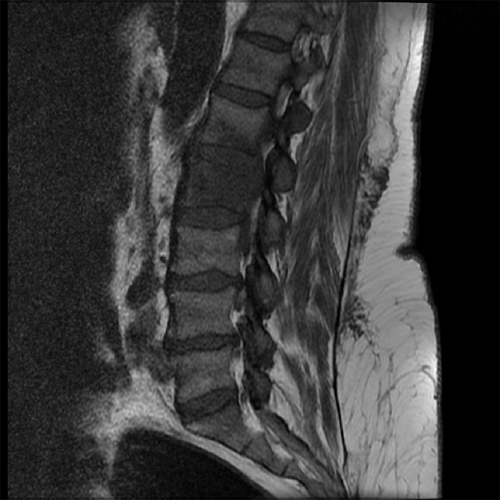

1. Accurate Diagnosis

An MRI scan, blood tests, and biopsy (if needed) help confirm the diagnosis. Dr. Tungish Bansal uses advanced imaging techniques and lab tests to pinpoint the infection.